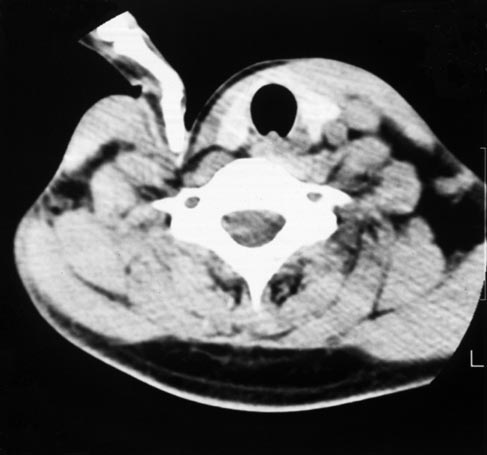

イメージ 1些か困難な刺入箇所というのが、星状神経節付近です。

現状はC3の神経根付近に刺入して、仮的なブロックを行っております。